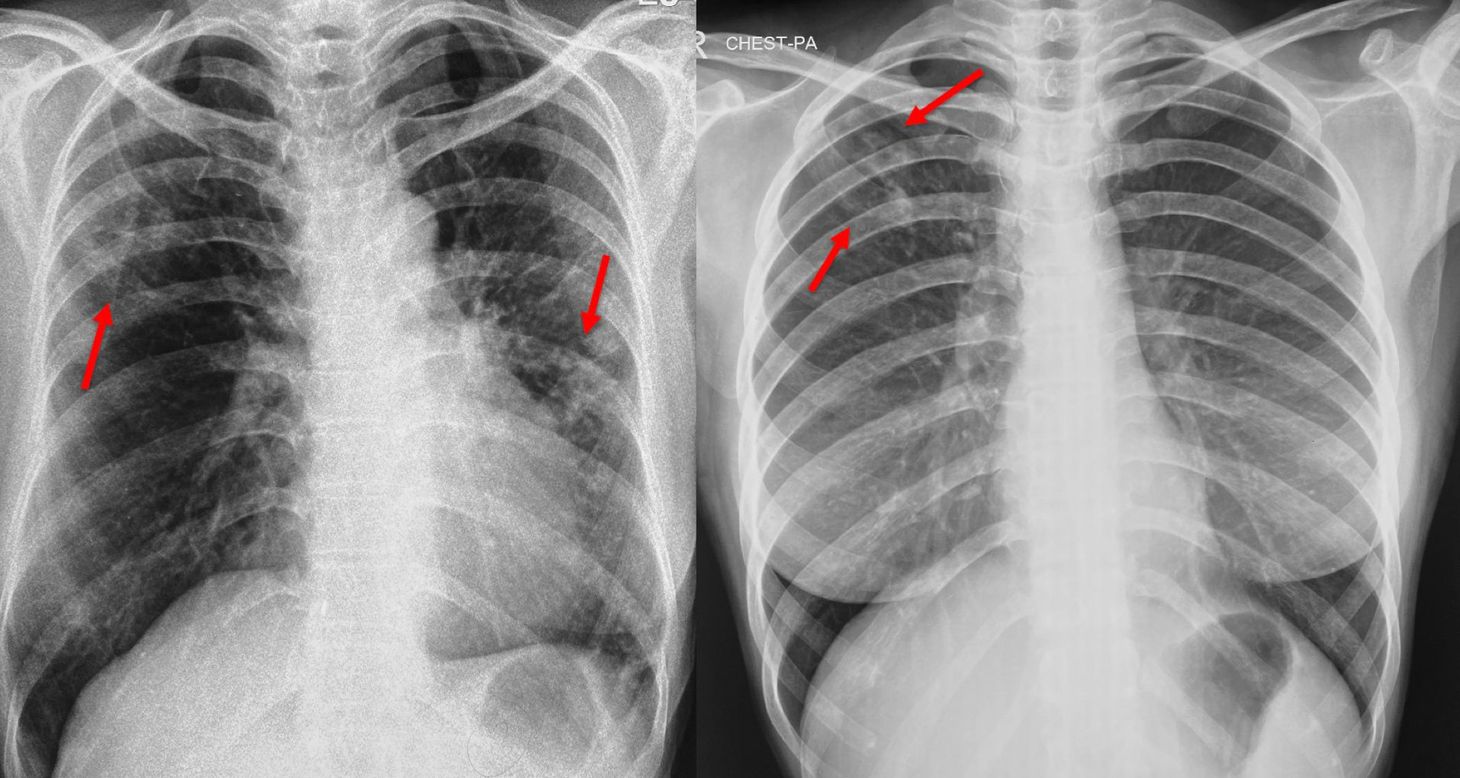

Chest X-ray for Screening for Tuberculosis

There are many ways to screen for TB, especially in the asymptomatic population. The Mantoux test and sputum testing with PCR are two such. Another is the chest X-ray, a simple tool that is available ubiquitously across the country. While a chest X-ray also has false positives and negatives, the recent upsurge of artificial intelligence (AI) tools that help interpret them reasonably accurately has again led to a lot of interest when it comes to mass screening.

Even at an individual level, doing a chest X-ray once in 3-5 years, will help. If the X-ray shows findings suggestive of active TB, even if the sputum remains negative, there is a 26% or so chance that the sputum will become positive in the next 3 years [2]. People who are infectious but asymptomatic are also “spreaders” of TB.

What does this mean for you and I? While there are no USPSTF like guidelines for the use of chest X-ray in the screening of TB in individuals (though there are WHO guidelines for mass screening), given the high burden of TB in India (at least one in 250 if not more) and therefore a reasonable chance of contracting TB in your lifetime, it is a good idea to check for TB by doing a chest X-ray, at least once in 3-5 years, as part of your annual health check-up.